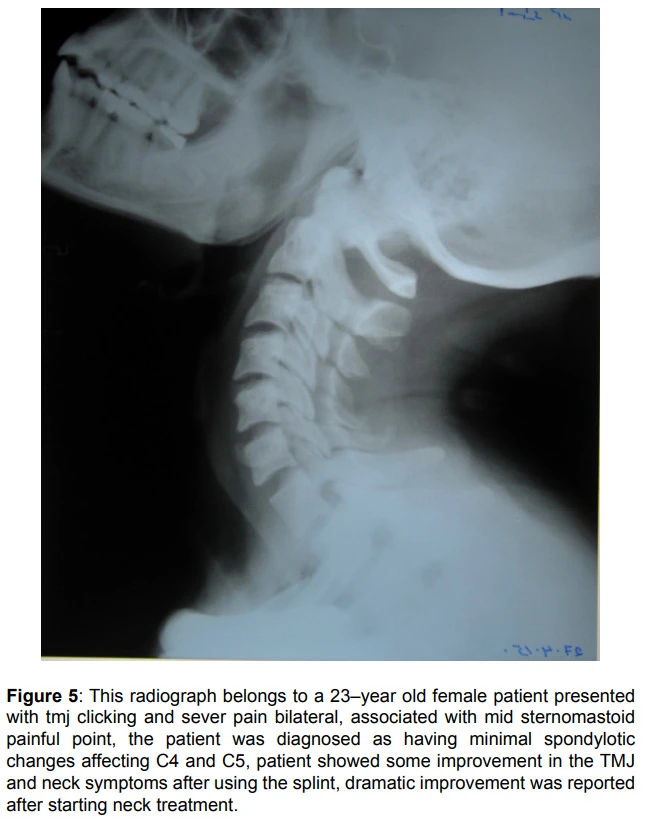

위의 사례는 좀 더 심각해보이는데요. 양측성 턱관절 통증과 턱관절 잡음을 호소하는 23세 여성의 영상 소견에서 C4, C5의 경추 문제가 보였고 턱관절의 균형을 잡는 스플린트 치료를 통해 턱관절과 목 증상이 개선되었고, 목 치료를 시작하면서 경추의 관절운동각도가 좋아졌다는 사례입니다.

그림출처: 위와 상동